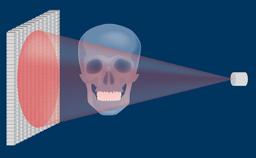

Todos os profissionais de saúde que fazem cirurgia de implante encontrarão complicações durante toda a vida profissional. Tais complicações podem ocorrer por várias razões diferentes, mas a maioria pode ser explicada como percalços ou erros cirúrgicos e/ou protéticos. Este módulo de aprendizado fornecerá uma visão geral das complicações cirúrgicas mais frequentes associadas à instalação do implante e discutirá o manejo em termos de medidas preventivas e estratégias de tratamento.

- descrever as complicações cirúrgicas mais frequentes relacionadas à instalação do implante